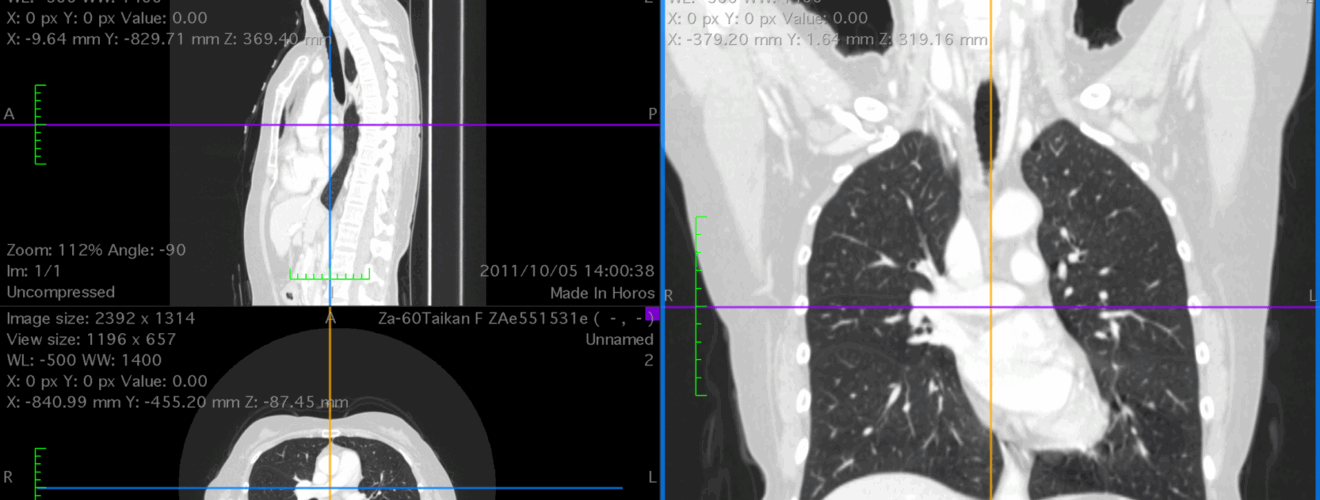

1. 解剖前に得られていたCT所見について、1つを選んで記入。2のCT画像についての説明もここに記す。どこのどの向きのスライスか、画像に追加した矢印などが何を指しているかなどを説明する。

• 【例】両側に胸水貯留がみられた。図はT7付近のスライス(肺野条件)。矢印は胸水を示す。

2. 1で述べたポイントのわかるCT画像をアップロード。着目するポイントを矢印などで明示する。DICOM画像からJPEG、PNGなどの画像ファイルに書き出すこと。複数の画像を組み合わせる場合には、あらかじめ1つの画像にまとめること。10MBまで。できればファイル名を「班番号-CT」とされたい(必須ではない)